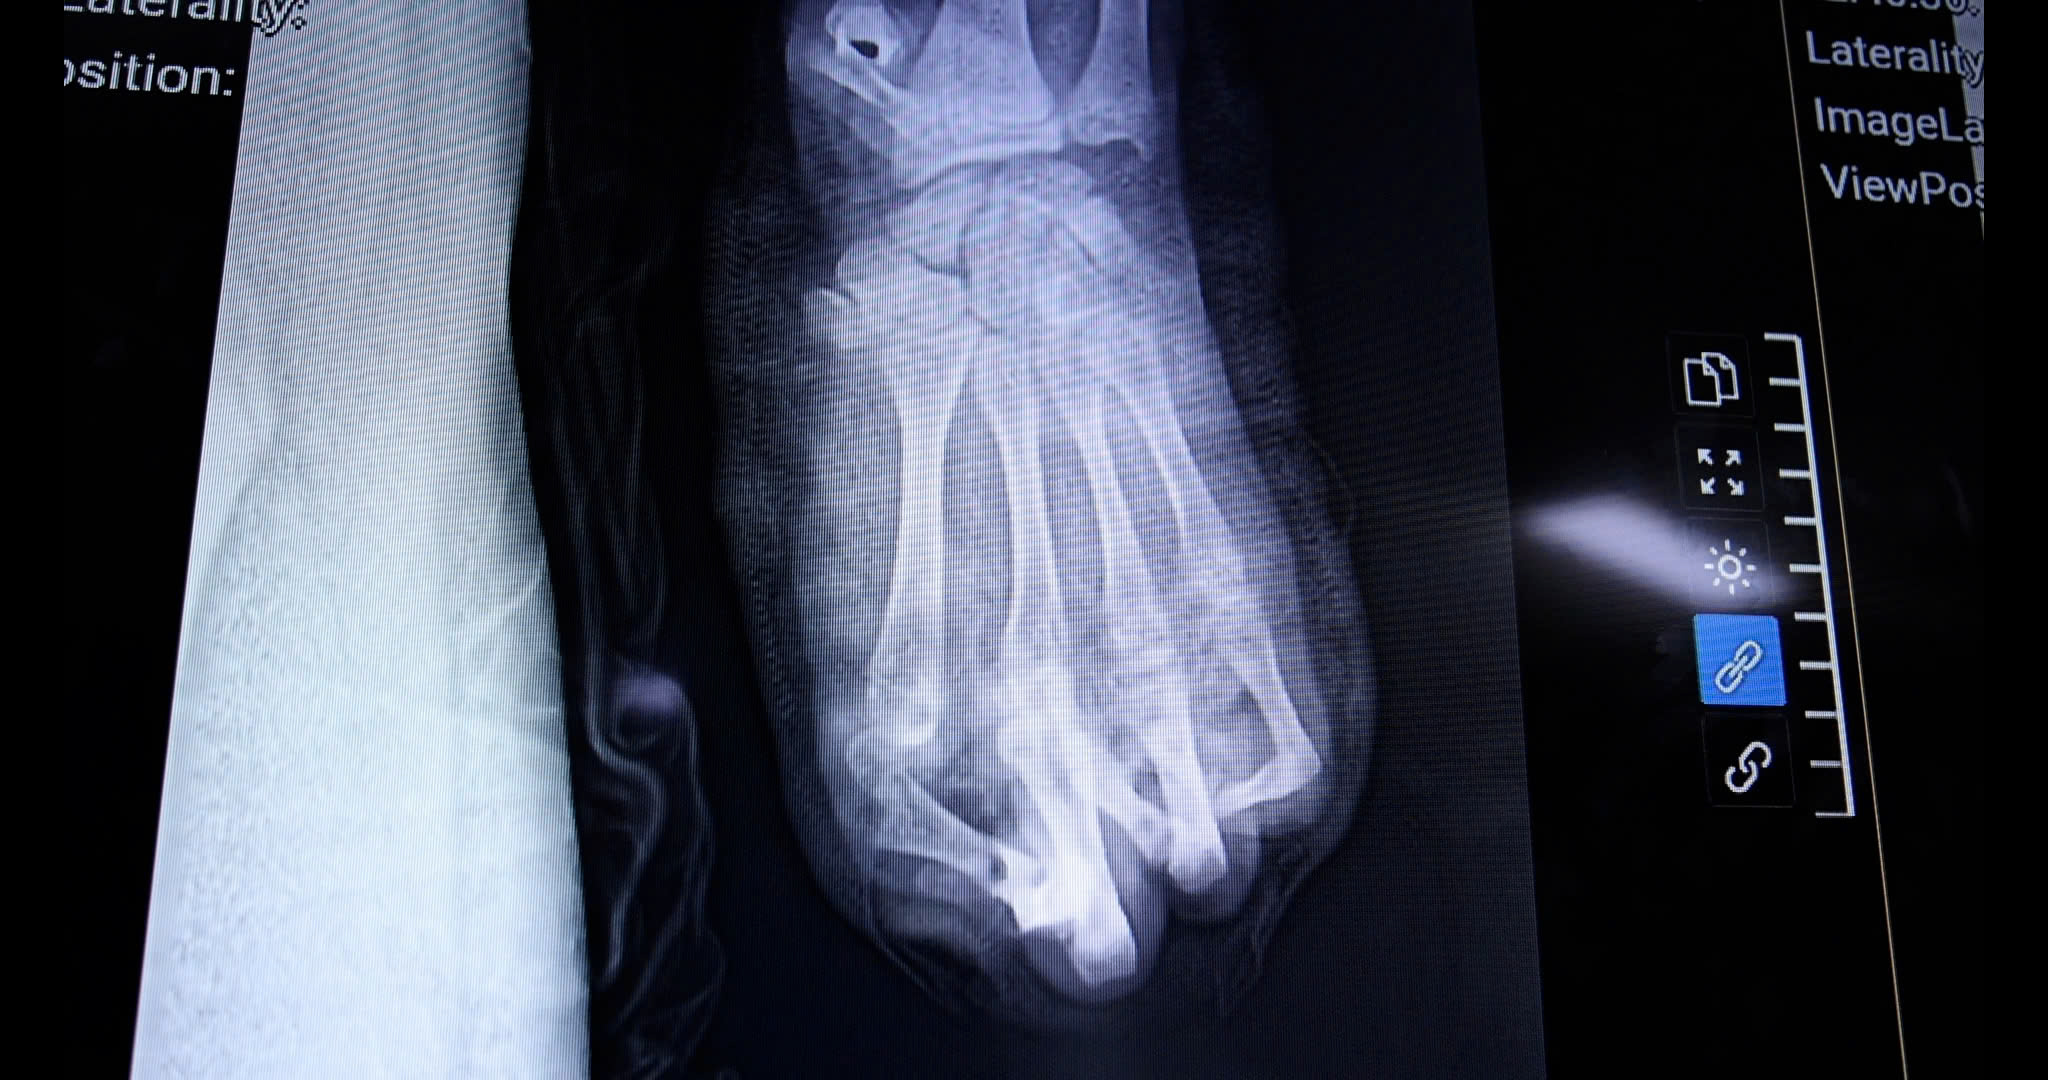

Bàn tay trái của nam thiếu niên bị dập nát và mất ngón do pháo nổ.

Dù được cấp cứu và phẫu thuật khẩn trương, sau nhiều nỗ lực của ê-kíp, các bác sĩ chỉ có thể giữ lại được 2 trong số 5 ngón tay cho người bệnh. Toàn bộ vùng gan bàn tay và cổ tay bị dập nát nặng, khiến quá trình điều trị dự kiến kéo dài, với nhiều cuộc phẫu thuật tiếp theo. Tiên lượng lâu dài, người bệnh có thể chỉ phục hồi được một phần chức năng rất hạn chế của bàn tay.

Hiện tại, người bệnh đã được cắt lọc tổ chức dập nát, lấy bỏ các dị vật là mảnh pháo. Trong thời gian tới, các bác sĩ sẽ tiếp tục điều trị che phủ các vùng hoại tử bằng vạt da và dự kiến sau vài tháng sẽ phẫu thuật chuyển ngón chân lên thay thế cho ngón tay cái đã mất. Nếu thuận lợi, người bệnh vẫn phải chấp nhận mất ít nhất 2 ngón tay vĩnh viễn.